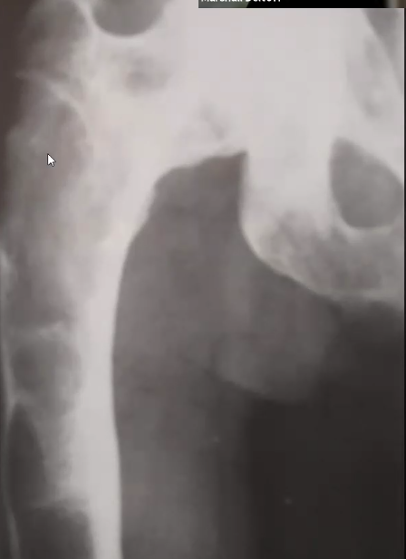

Kyste anévrismal osseux :

- ++ fémur, tibia et fibula (80%)

- Bénin mais ++ risque de fx patho car le cortex est aminci et l’os est « expanded